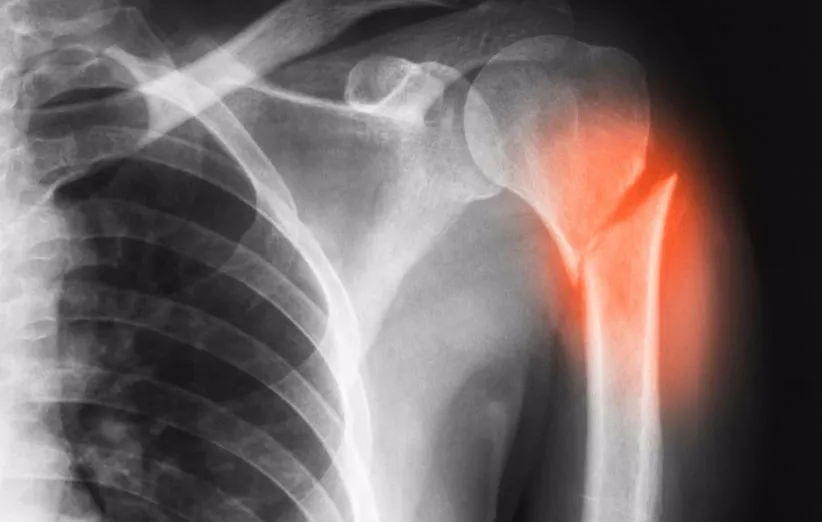

گروهی از محققان بیمارستان بومانت (Beaumont) به این یافتههای پیشبالینی رسیدهاند که در نشریهی «نانومدیسین» (Nanomedicine) منتشر خواهد شد. آنها عنوان کردند که میتوان از مادهی زیستتخریبپذیر برای درمان استخوانها در صدها هزار بیمار استفاده کرد؛ بیمارانی که پس از عمل برداشتن تومور، جراحی فیوژن ستون فقرات یا شکستگی استخوان به پیوند استخوان نیاز دارند.

معمولا در پیوند استخوان به استخوانی از بخش دیگری از بدن بیمار نیاز است که به نوبهی خود نیاز به یک جراحی دیگر دارد و مشکلات و ریسکهای این پروسه را بیشتر میکند. استخوانهای اهداشده هم به عنوان گزینهی دیگری قابل استفاده هستند، اما بسیار به ندرت میتوان به آنها دسترسی داشت.